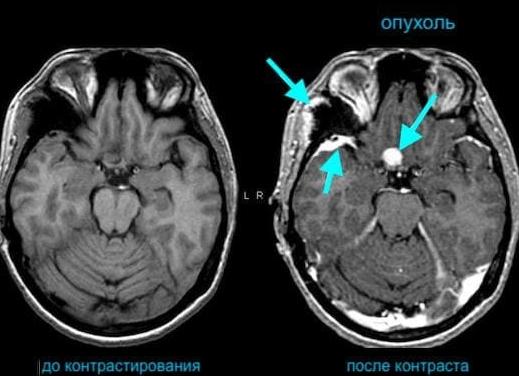

Магнитно-резонансная томография (МРТ) — один из молодых методов диагностики серьёзных патологий. Невзирая на факт высокой информативности и безопасности обследования, многие пациенты всё же сомневаются перед прохождением сканирования. Вредна ли МРТ? Актуальность этого вопроса сохраняется и по сегодняшний день.